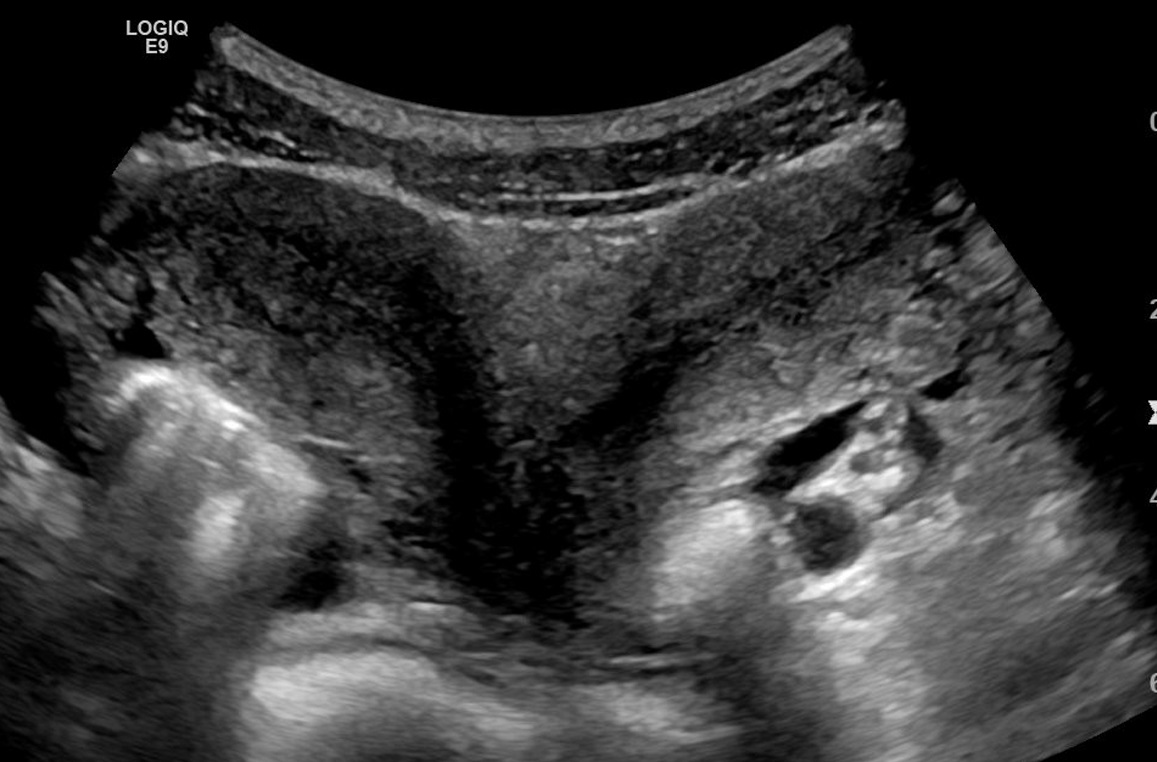

There are conditions that prompt duplications in the uterine, vaginal and cervical realms. The Müllerian duct reflects the precursor structures that embryologically morph to become the reproductive tract - when there is a deviation from normal development or a failure to fuse properly, anomalies arise. Müllerian duct anomalies (MDAs) can run in families and on one end of the spectrum can produce a double vagina, double uterus with dual cervices, aka Uterine Didelphys. This is the congenital anomaly being reported in this case.

Such atypical pelvic organs can result in several varieties (e.g. double uterus, single vagina or double everything). These are often diagnosed upon first menstruation or when issues with fertility come into play. With the former, one vaginal canal might end in a blind pouch so blood will accumulate with an inability to flow out of the body and great discomfort will arise. Upon investigation and proper medical evaluation, the discovery will be made. The latter reality might also lead to determining such an underlying cause.